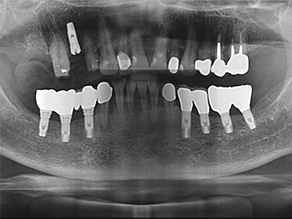

하단의 치료 사례는 10년 이상 된 단골 환자분들로 세월이 지남에 따라 임플란트 수가 늘고 있어 안타까운 마음도 들지만,

임플란트로 본인 치아처럼 새 치아를 얻어 오랜 세월 잘 드실 수 있도록 최선을 다해 임플란트 치료를 하고 있습니다.